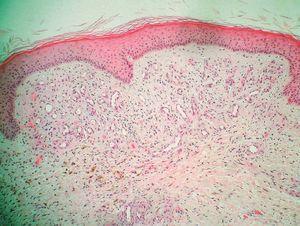

El estudio histopatológico evidenció un aumento en el número de capilares neoformados en la dermis superficial y media. Alrededor de esta proliferación vascular se veía un ligero infiltrado inflamatorio crónico y depósitos de hemosiderina en la dermis profunda. La epidermis suprayacente era normal (fig. 2).

Figura 2. Hematoxilina-eosina, x100.

La histopatología del proceso es característica, con un incremento en el número de capilares, de paredes gruesas, con extravasación de hematíes y depósitos de hemosiderina afectando a la dermis papilar en el caso de la acroangiodermatitis de Mali, y a todo el espesor de la dermis en el síndrome de Stewart-Bluefarb.